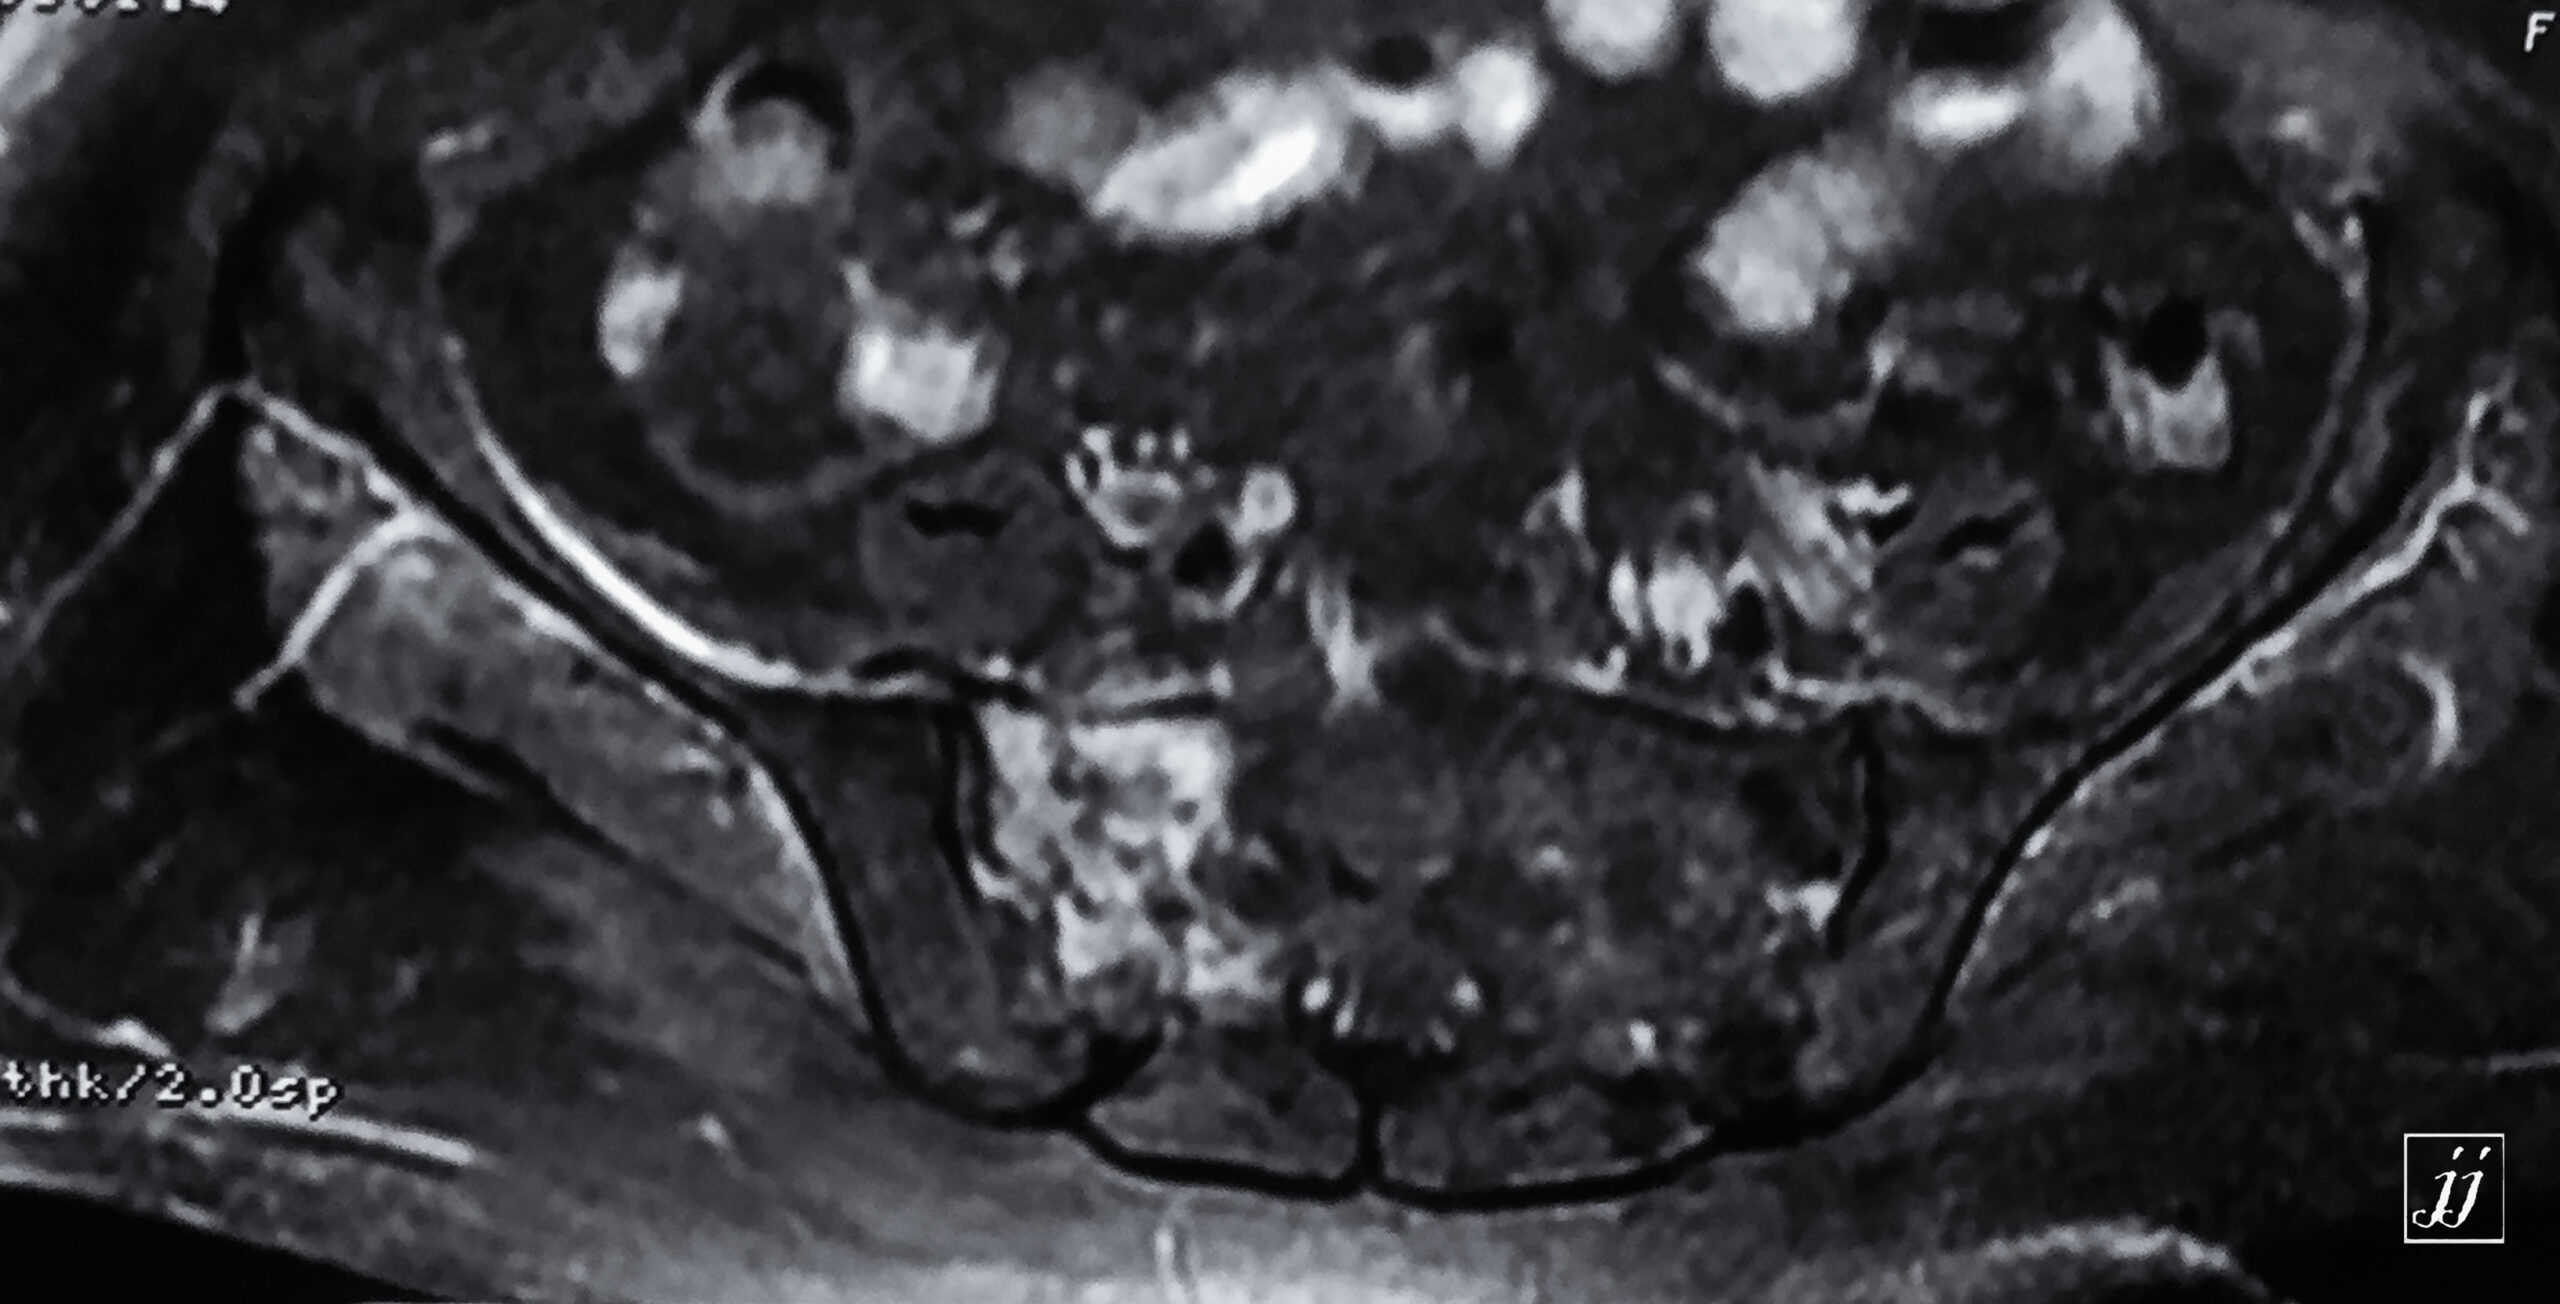

MSK- right pelvic floor muscular rupture and abnormal signal of right sacrum and pubic fracture (9)